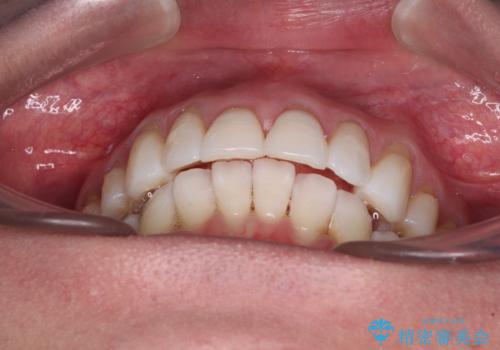

- 上の前歯の出っ歯を治したいとのことで来院された患者様です。

後戻りによる再矯正というもともあり、インビザラインを希望されていました。

上顎の歯は後方移動とIPR(歯と歯の間を削る)によって口元が引っ込むように、下顎は歯列全体の拡大とIPRによって上顎とバランスよく咬み合うように設計し、インビザラインにより治療を行うこととしました。

治療を開始して暫くして、勤務先から2年以上帰国することができず、それまでの移動がほとんど後戻りしてしまい、帰国後に再度後戻りをリカバリーするための治療を行うこととなりました。

5年以上の治療期間がかかりましたが、気になっている部分を改善することができました。